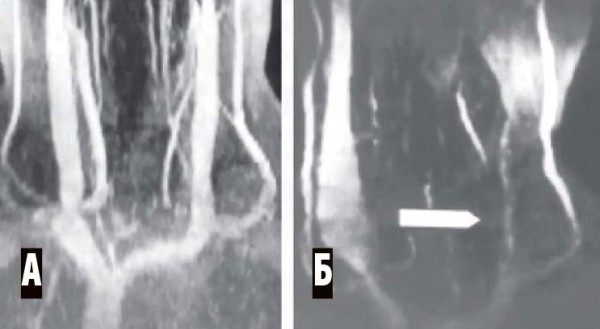

Магнитно-резонансная венография (аппараты МРТ имеют специальную программу для такого исследования). Исследуются синусы головного мозга, а также вены шеи. Всегда сравниваются правая и левая стороны (см. рис. 4, 5).

Рисунок 5. МР-венография при тромбозе синусов. А — левая сторона, обнаружено отсутствие сигнала от левых поперечного и сигмовидного синусов (признак тромбоза). Б — правая сторона, кровоток по синусам в норме.

При дорсопатии: лучевая диагностика — МРТ позвоночника, шейная спондилография (обязательно 5 проекций, включая трансоральную спондилограмму), а также

МР-венография брахиоцефальных вен (см. рис. 6).

Рисунок 6. МР-венограмма. Мышечная компрессия внутренней яремной вены. А — брахиоцефальные вены в норме, Б — сдавление левой внутренней яремной вены гипертрофированными нижними шейными мышцами (уровень сдавления показан стрелкой). Противоположная внутренняя яремная вена компенсаторно расширена.